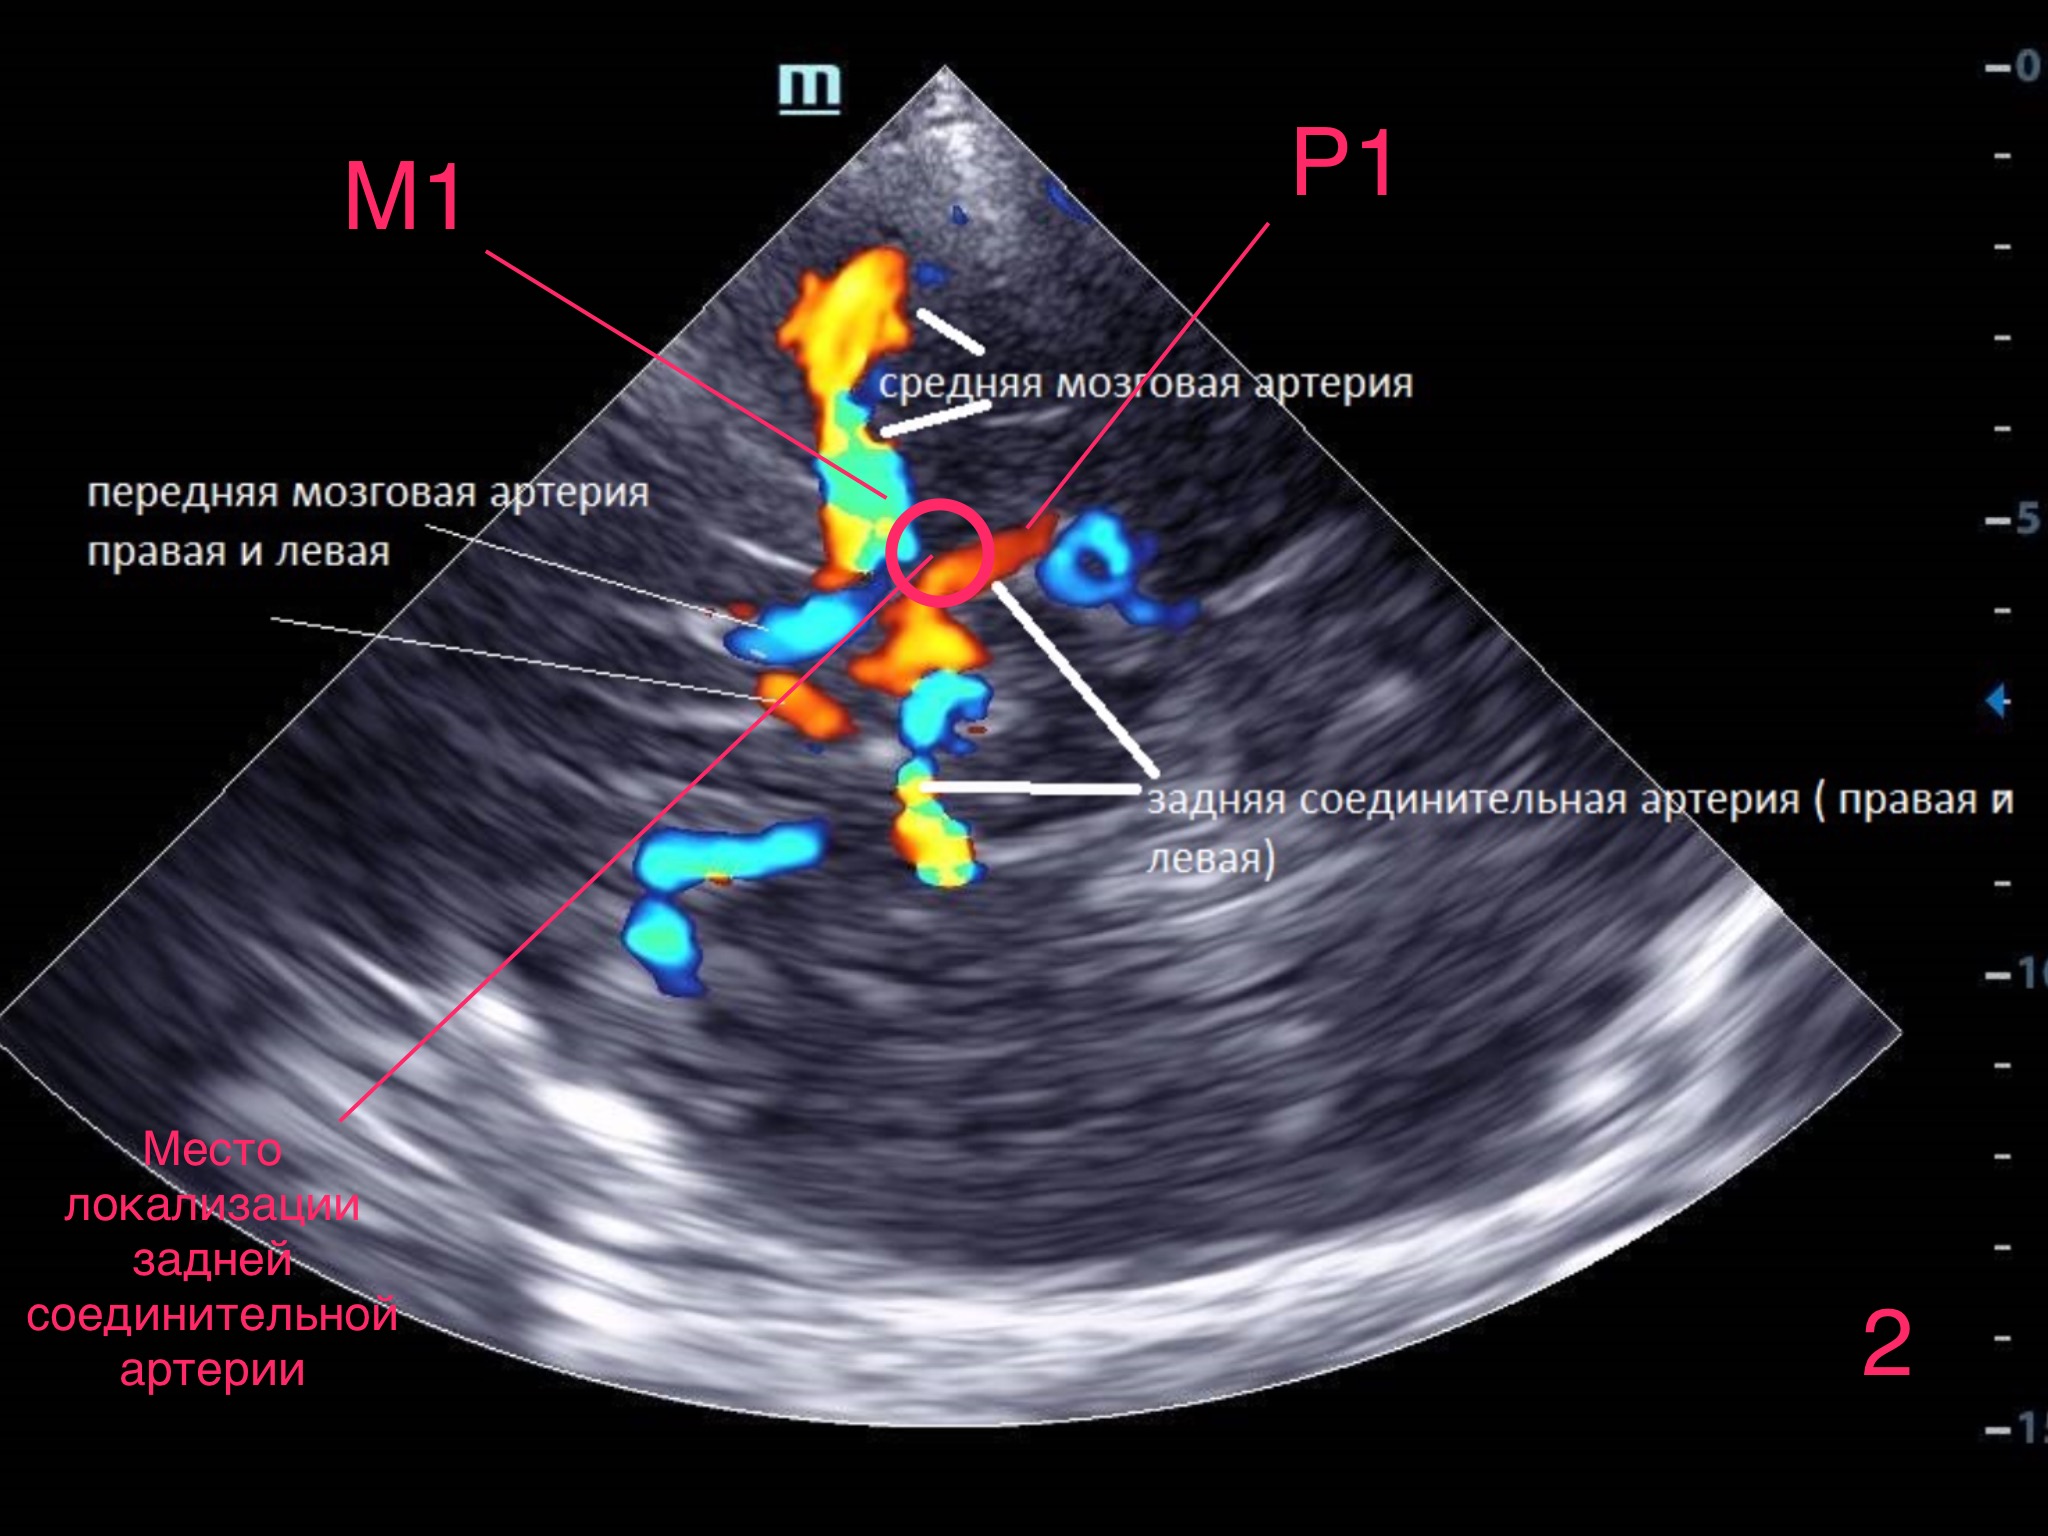

УЗИ, МРТ при аневризме вены Галена (АВГ) у плода

Диагностика аневризмы мальформации вены Галена по КТ, МРТ, УЗИ, ангиограмме . а) Терминология : 1 . Сокращения : • Вена Галена (ВГ), аневризмальная мальформация вены Галена (АМВГ), срединная прозенцефалическая вена (СПВ) - вена Марковского . 2 .

Видео: аневризмы вены Галена на УЗИ Мальформация большой вены мозга Мальформацией вены Галена называют изменение сосудистой системы, при котором обнаруживается сплетение в виде клубка, состоящего из сосудов эмбрионального типа и обязательно — расширенной большой вены (аневризма) .